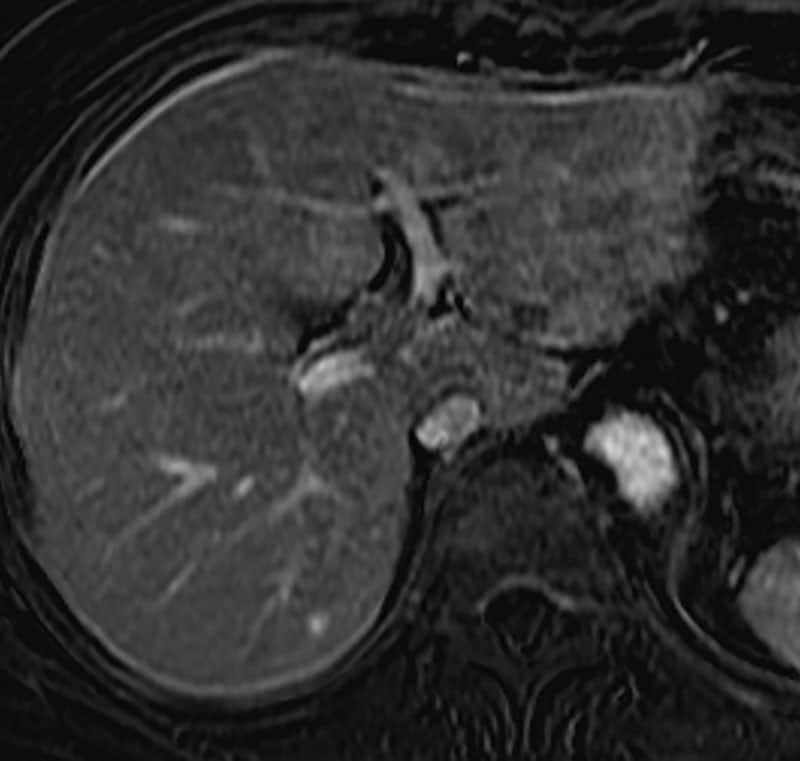

図4.造影T1WI肝細胞相

肝S2結節に明瞭なEOB取り込み低下を認める。

CTでは指摘困難かつ、PET-CTで軽度集積を認めるのみの肝転移病変に対して、EOB-MRIでは拡散低下とともに肝細胞造影相において明瞭なEOB取り込み低下を認め、化学療法再開に繋がった。PET-CTでは肝臓の生理的集積により判断が難しい病変においても、当症例において EOB-MRI は肝転移病変を鋭敏に検出することができたため、肝転移の確定診断に有用であった。